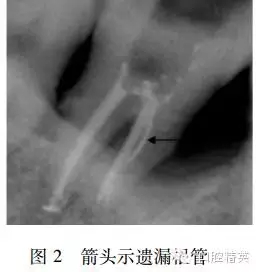

數(shù)字化X線攝影示:7遠(yuǎn)中根根管充填恰填致密,近中遺漏根管(圖2)。去除近中根管內(nèi)回填牙膠,GG鉆擴(kuò)大根管口,根管顯微鏡下在根管中段偏近中舌側(cè)找到根管口,根管測(cè)長(zhǎng),預(yù)備,消毒,試尖(圖3),充填,術(shù)后X線片顯示恰填(圖4)。